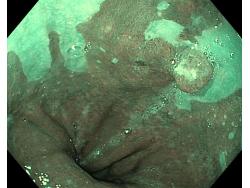

Przełyk Barretta